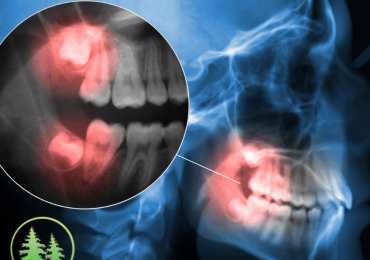

Root Canals

Expert root canal care to ease discomfort and restore your smile with trusted expertise.